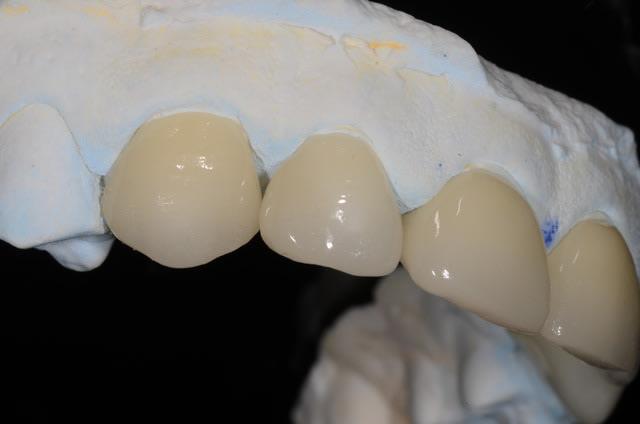

après avoir bien galéré avec la version 3.85 je mets en ligne un cas de 6 cérams faites à partir des modèles scannés avec cerec.

D'abord les biscuits, modèles d'origine (2005), situation actuelle, puis couronnes glacées.

Blocs VITA Triluxe Forte 12.